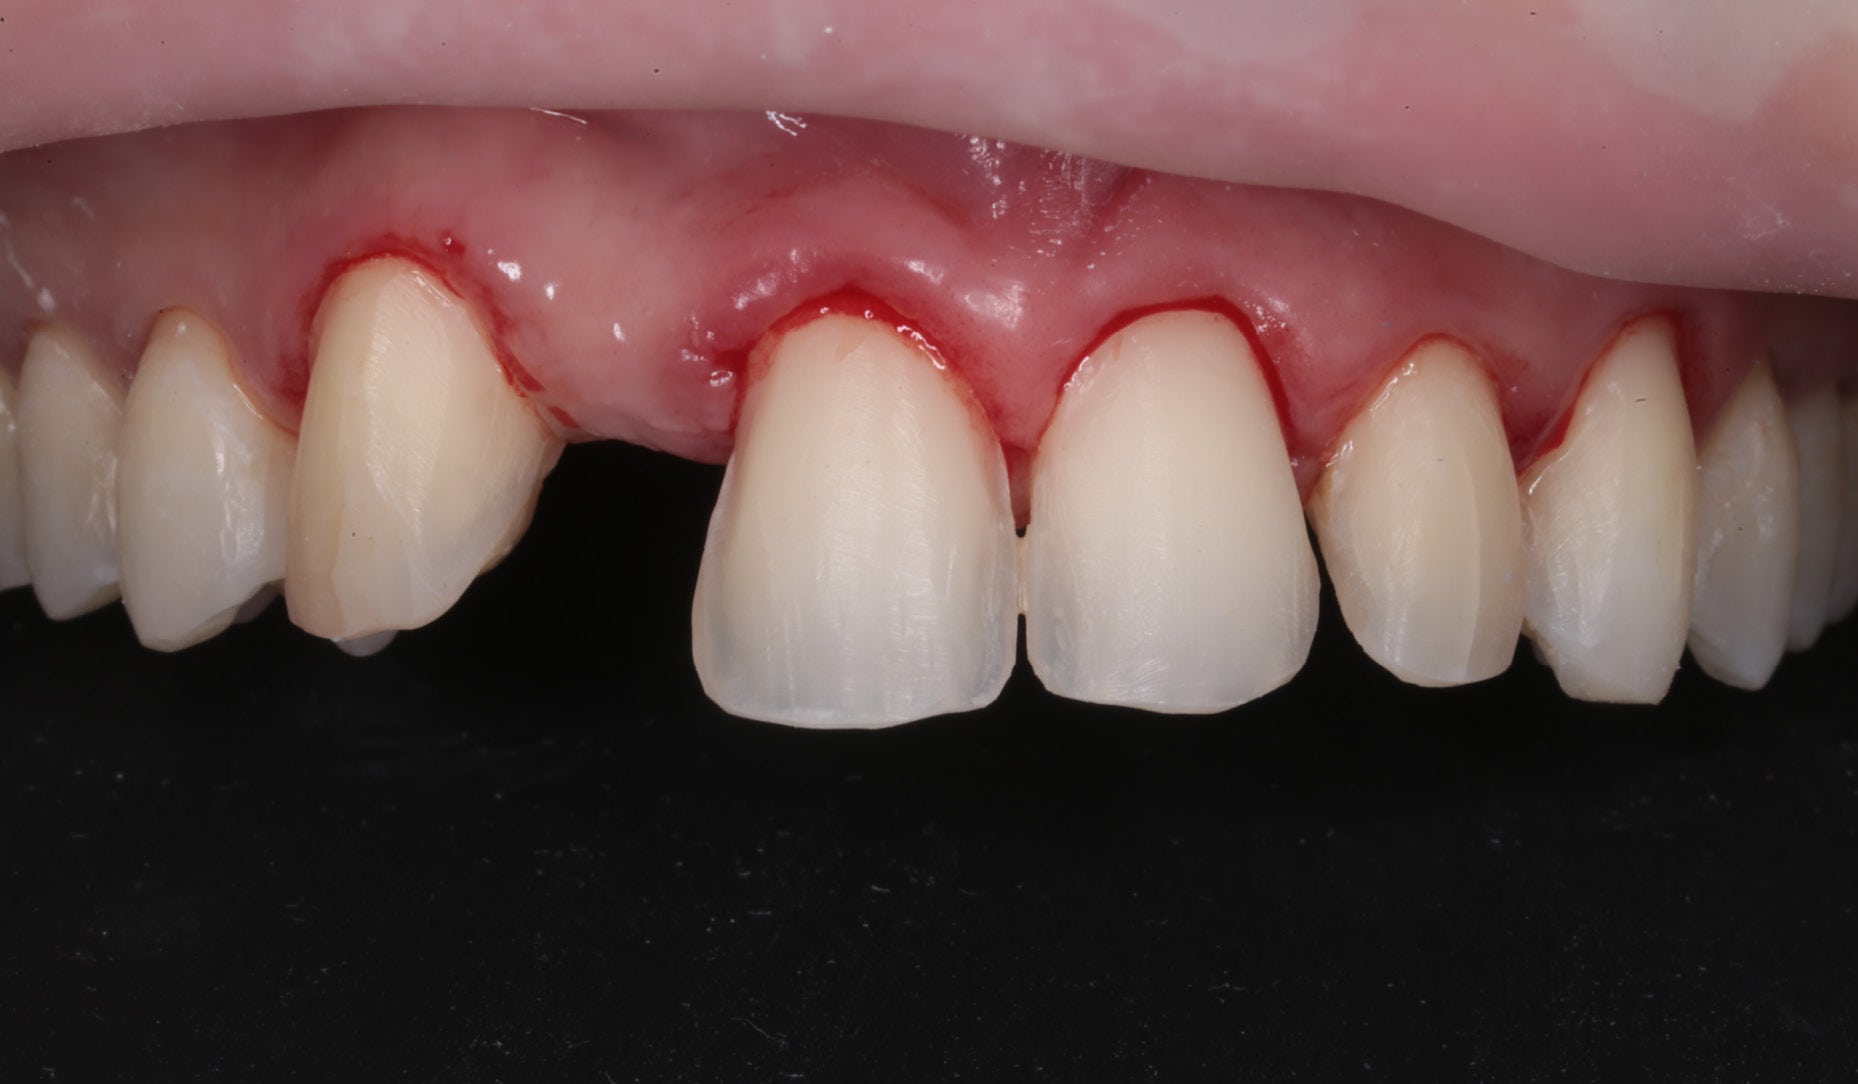

Clinical Cases, Labside Two high-strength ceramics, one micro-layering system Case by DT Andreas Chatzimpatzakis AESTHETIC AND EFFICIENT SMILE MAKEOVER Most patients asking for a smile makeover desire custom solutions rather than an off-the-peg smile: Individual tooth shapes that fit their face and their character, an internal play of colours that matches their age and natural dentition. Modern dental materials allow us to deliver what they demand in many situations – usually at a reasonable price. For a long time, however, we have been facing challenges when combining cosmetic and medically indicated treatment – e.g. a smile makeover including the rehabilitation of a missing lateral incisor. A straightforward solution – using lithium disilicate veneers alongside a zirconia cantilever bridge, both finished with their respective porcelain systems – would have been complicated by potential differences in the final appearance. With CERABIEN™ MiLai (Kuraray Noritake Dental Inc.), a set of internal stains and porcelains designed for micro-layering, the situation is different: Suitable for micro-layering on zirconia and lithium disilicate, it supports its user ideally in creating a harmonious smile even when the two framework materials are combined. A NEW CUSTOM SMILE The following patient case is a perfect example: A female patient with a missing lateral incisor, multiple visible composite restorations in the anterior region and an enamel fracture at her incisal edge desired a smile makeover. The selected materials were Amber Press LT (HASS), shade A1, for four veneers on the central incisors and the left lateral incisor and canine (teeth # 11, 21, 22 and 23 according to the FDI notation) and KATANA™ Zirconia YML (Kuraray Noritake Dental Inc.), shade A2, for the planned cantilever bridge on the maxillary right canine, replacing the missing lateral incisor (teeth # 12 and 13). Fig. 1. Female patient with a missing maxillary lateral incisor and multiple composite restorations in the anterior area – a smile makeover is desired. Fig. 2. Patient with mock-up. Fig. 3. Minimally invasive preparation through the mock-up, which takes into account the minimum space required for the planned materials and restorations. Fig. 4. Teeth prepared for the all-ceramic restorations. Fig. 5. Occlusal view of the maxillary teeth after tooth preparation. Fig. 6. Full-contour veneers and cantilever bridge on the model. Fig. 7. Restorations after a cutback limited to the vestibular and incisal area. Fig. 8. CERABIEN™ MiLai LT1 is applied to the middle and cervical area of the zirconia cantilever bridge. Fig. 9. CERABIEN™ MiLai Value Liner 2... Fig. 10. … and Value Liner 1 applied to the incisal area of the central and lateral incisor restorations. Fig. 11. CERABIEN™ MiLai porcelain Creamy Enamel mixed with Value Liner 2 (70/30) added to the middle and cervical areas of the four lithium disilicate restorations to increase and control the value. Fig. 12. ... while E2 is added to the incisal area of both canines. Fig. 13. Restorations covered by a layer of Tx ... Fig. 14. ... and LTx. Fig. 15. Appearance of the restorations after the first bake. Fig. 16. Adding translucency and opalescence to the cervical area with LT1 and brightness to the ridges with Creamy Enamel. Fig. 17. Completion of the enamel surface with a cover layer of LTx, which is responsible for a high translucency and opalescence. Fig. 18. Result of the second bake. Fig. 19. Final restorations with a natural self-glaze effect on the model. Fig. 20. Final restorations with a natural self-glaze effect in the patient’s mouth. Fig. 21. Smooth optical integration of the restorations. Fig. 22. Beautiful treatment outcome. CONCLUSION With the described approach and selected materials, it was possible to create restorations with a natural shade, shape and texture. They matched not only the appearance of the remaining natural teeth, but also showed internal consistency across the selected framework materials. The technical procedure was quite straightforward and efficient, while the result speaks for itself. Special thanks to Dr. Kanellos Ioannis for the collaboration on this case and for kindly providing the pre- and post-treatment photographs that complemented it. Dental technician: ANDREAS CHATZIMPATZAKIS Based in Athens, Greece, Andreas Chatzimpatzakis is the founder and director of ACH Dental Laboratory (since 2000), specializing in refractory veneers, lithium disilicate, zirconia, and implant prostheses. He graduated in Dental Technology from the University of West Attica and received advanced training in all-ceramic restorations in Helsinki and Japan under renowned masters including Shigeo Kataoka. Since 2017, he has served as an international trainer for Kuraray–Noritake Dental Inc., delivering lectures and hands-on courses worldwide on advanced ceramic techniques. He has also held roles as Key Opinion Leader for MPF Brush Co., Ambassador for Hass Co., and Editor-in-Chief of Laborama. An active member of the Hellenic Academy of Aesthetic Dentistry, his work and articles have been published in both Greek and international journals. Jan 21, 2026 Dental Technician Kuraray Noritake Prosthodontics Clinical Case Katana Zirconia YML CERABIEN MiLai Prosthetic dentistry Lab Dental Ceramics Cad Cam Discs KATANA Zirconia YML View Product CERABIEN MiLai View Product Subscribe to our Newsletter Join thousands of dental professionals and receive free advice that can help you and your career. We will not spam or share your e-mail.